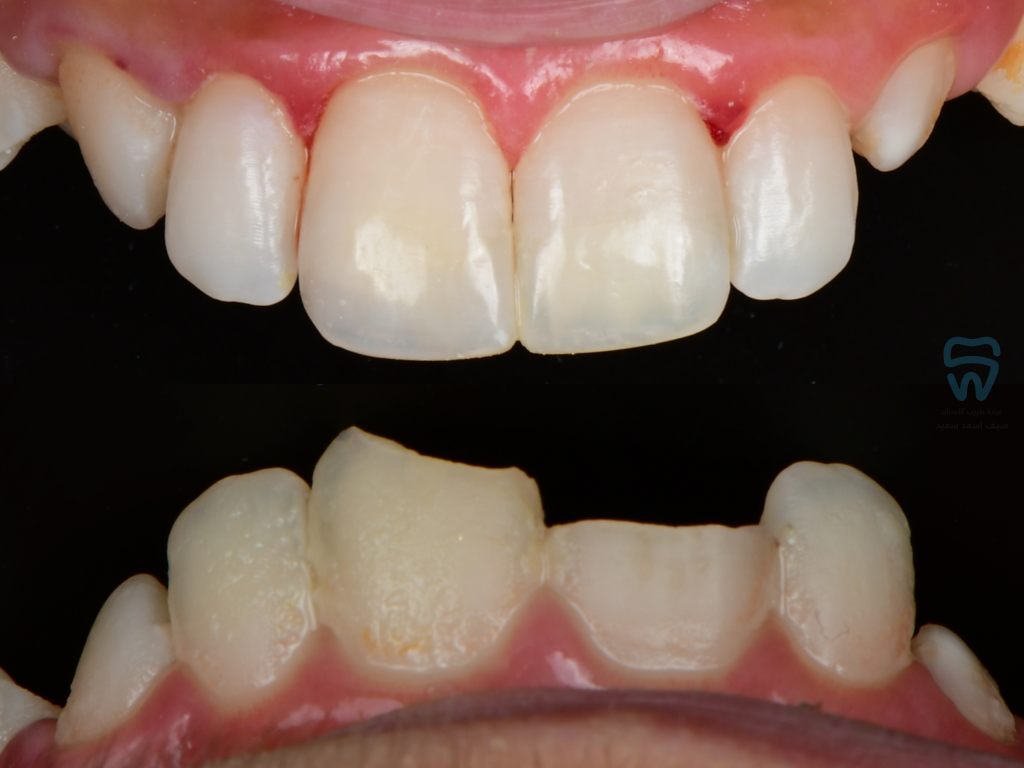

patient came with 2 fractured upper centrals

closer look at the condition

Complicated crown fracture